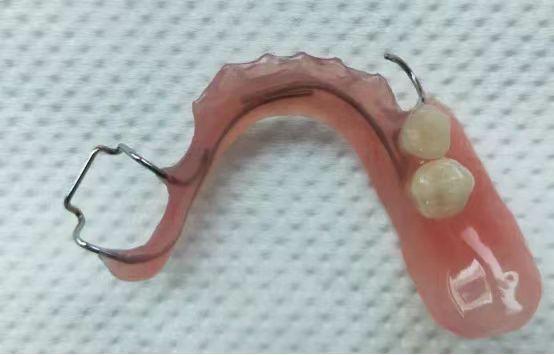

可摘式间隙保持器

主要适用于单颗或多颗乳牙早失的治疗,在保持间隙的同时,还能恢复部分咀嚼功能。